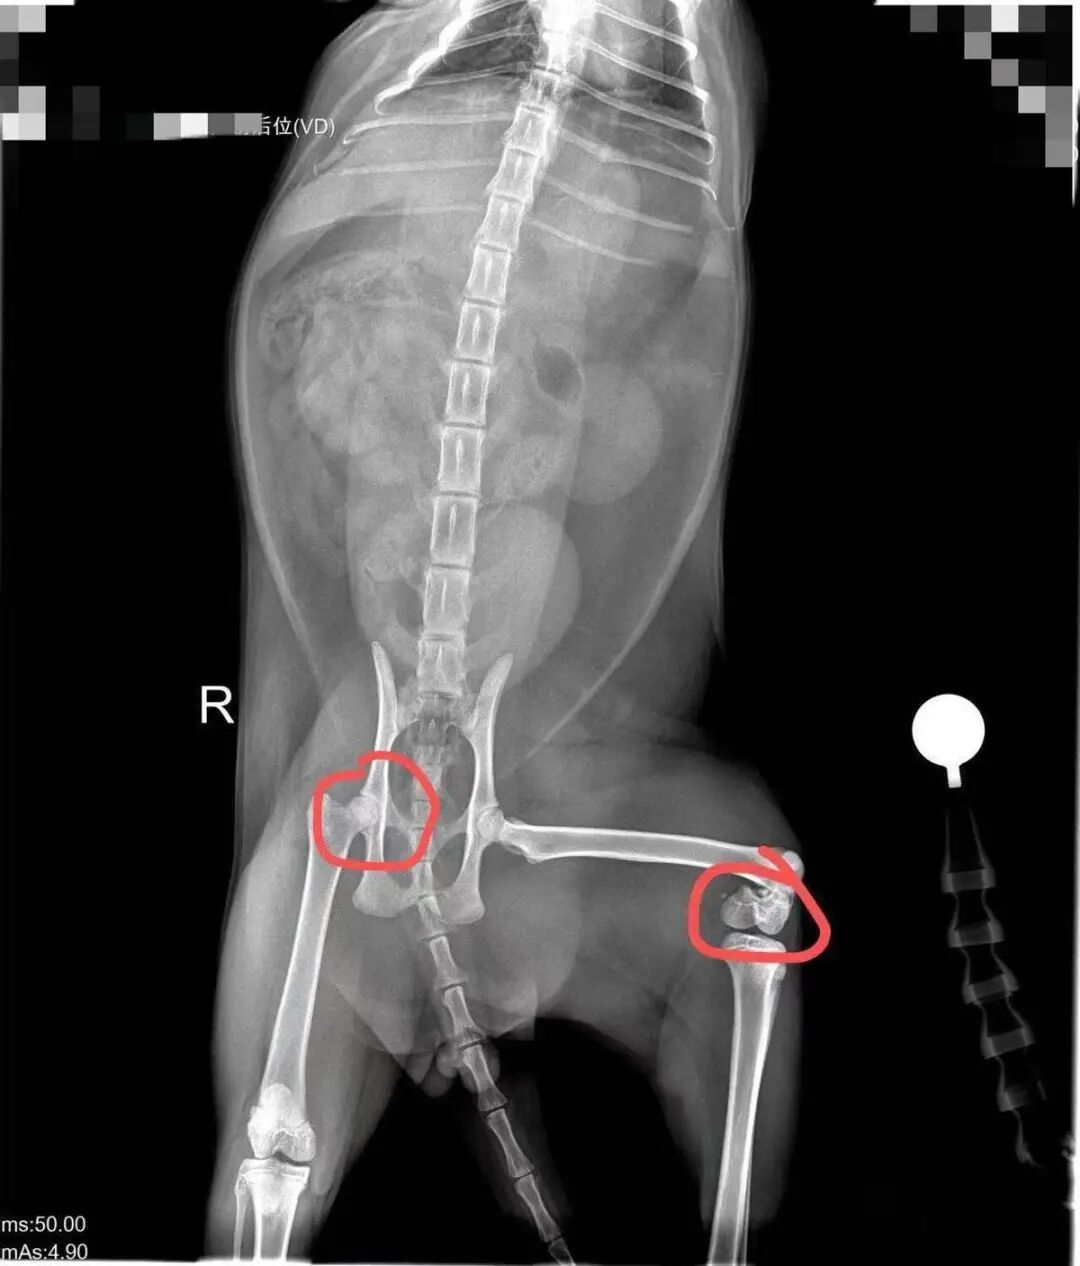

叶青的小猫从不及50厘米高的床上跳下后,突发右腿骨裂、左腿骨折。医师指出,这样矮的床不可能变成这种毁伤,小猫很可能自身骨头就存在问题。她也雷同要求商家提供健康解释。宠小皮干系售后客服均回复,无法提供小猫领养时的健康解释。

叶青的猫咪现在右腿骨裂、左腿骨折